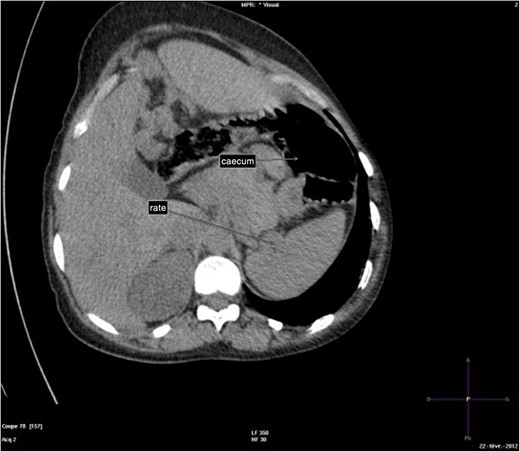

The abdominal-pelvic CT-scan showed a pre-splenic left position of the caecum and right colon, with no part of the colon on the right. The radiologist concluded that the patient was suffering from a complication of intestinal malrotation (IM) (Figs 1, 2, 3).

Abdominal-Pelvic CT-scan, non-contrast enhanced, in the sagittal plan, eleventh dorsal vertebra level.